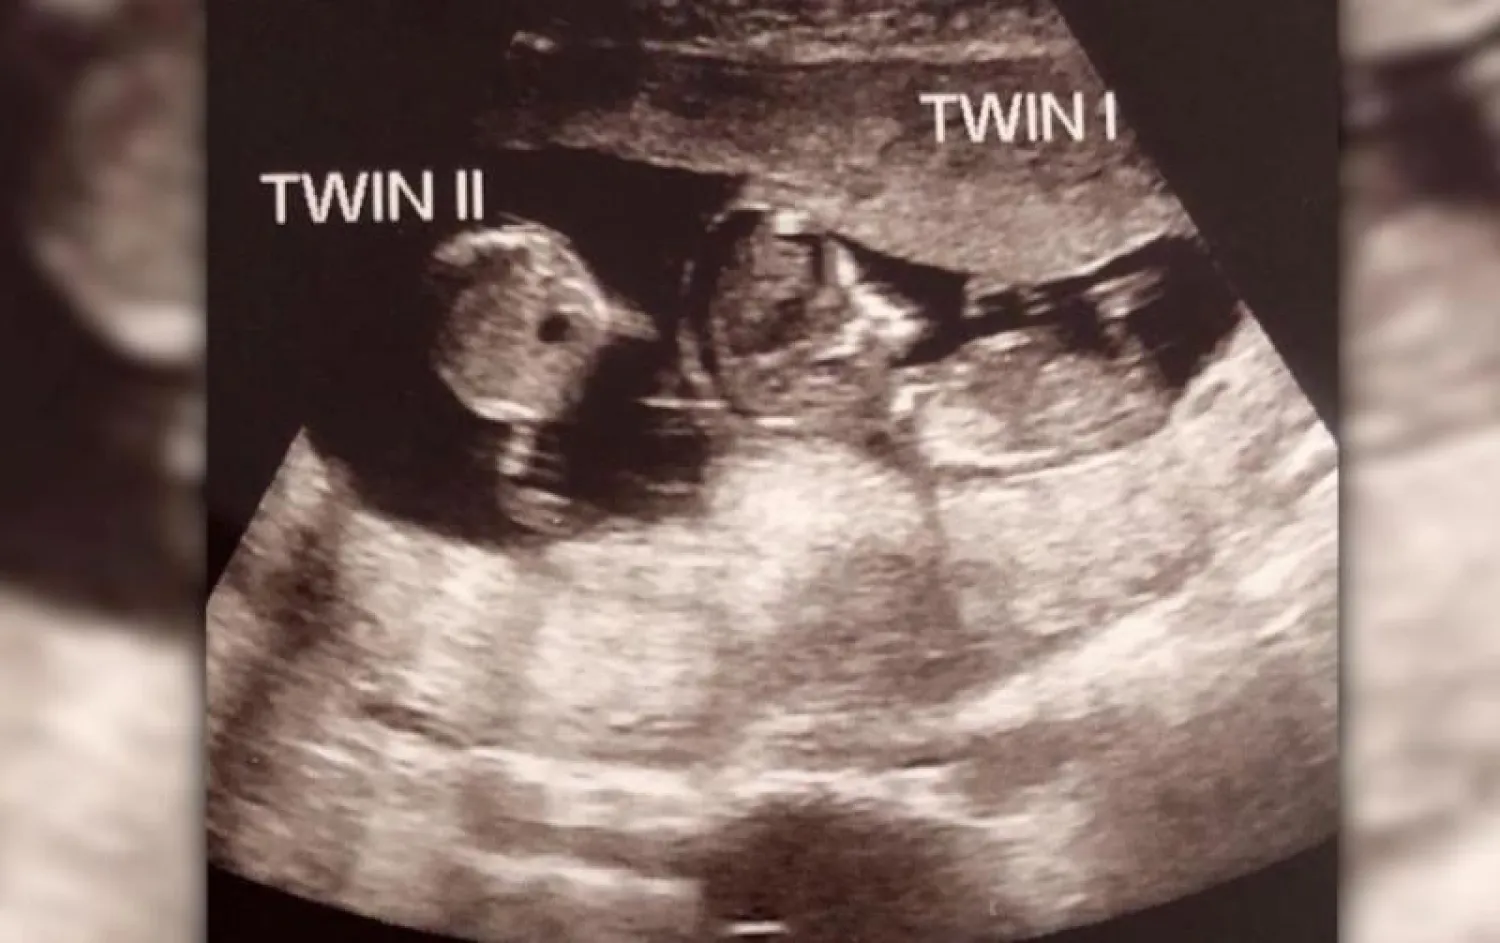

وفي أثناء خضوع ريبيكا للفحص بالموجات فوق الصوتية، فوجئت بإخبار الطبيب لها بأنها حامل بجنين آخر في الأسبوع التاسع، فيما كانت تحمل جنينها الأول منذ 12 أسبوعاً.

وأوضحت ريبيكا أن الأطباء أخبروها بأن الطفلين قد حُملوا في الواقع بفارق ثلاثة أسابيع. وأضافت وهي تضحك: «لم أصدق أن ذلك حدث لي. لكنه أمر جميل حق. أشعر كأنني فزت في اليانصيب».